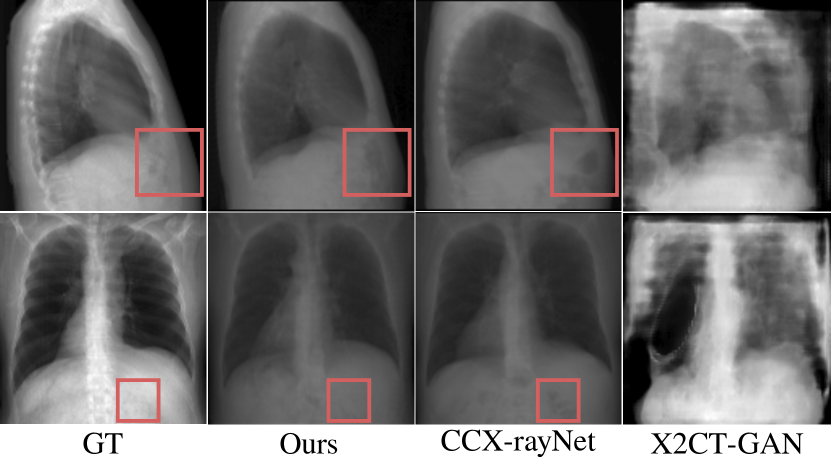

In Table 2 we compare our approach to paired alternative methods in terms of quality of the 3D outputs for both in- and out-of-distribution inputs. Despite variations in datasets originating from different imaging systems, resolutions, and patients’ health conditions, our model demonstrates superior performance across all metrics and maintains consistency across all out-of-distribution datasets. Refer to Figures 5 and 9 for qualitative results.

Figure 9: Examples of the correlated 3D projections from our proposed approach compared to alternative supervised methods X2CT-GAN [49] and CCX-rayNet [35].